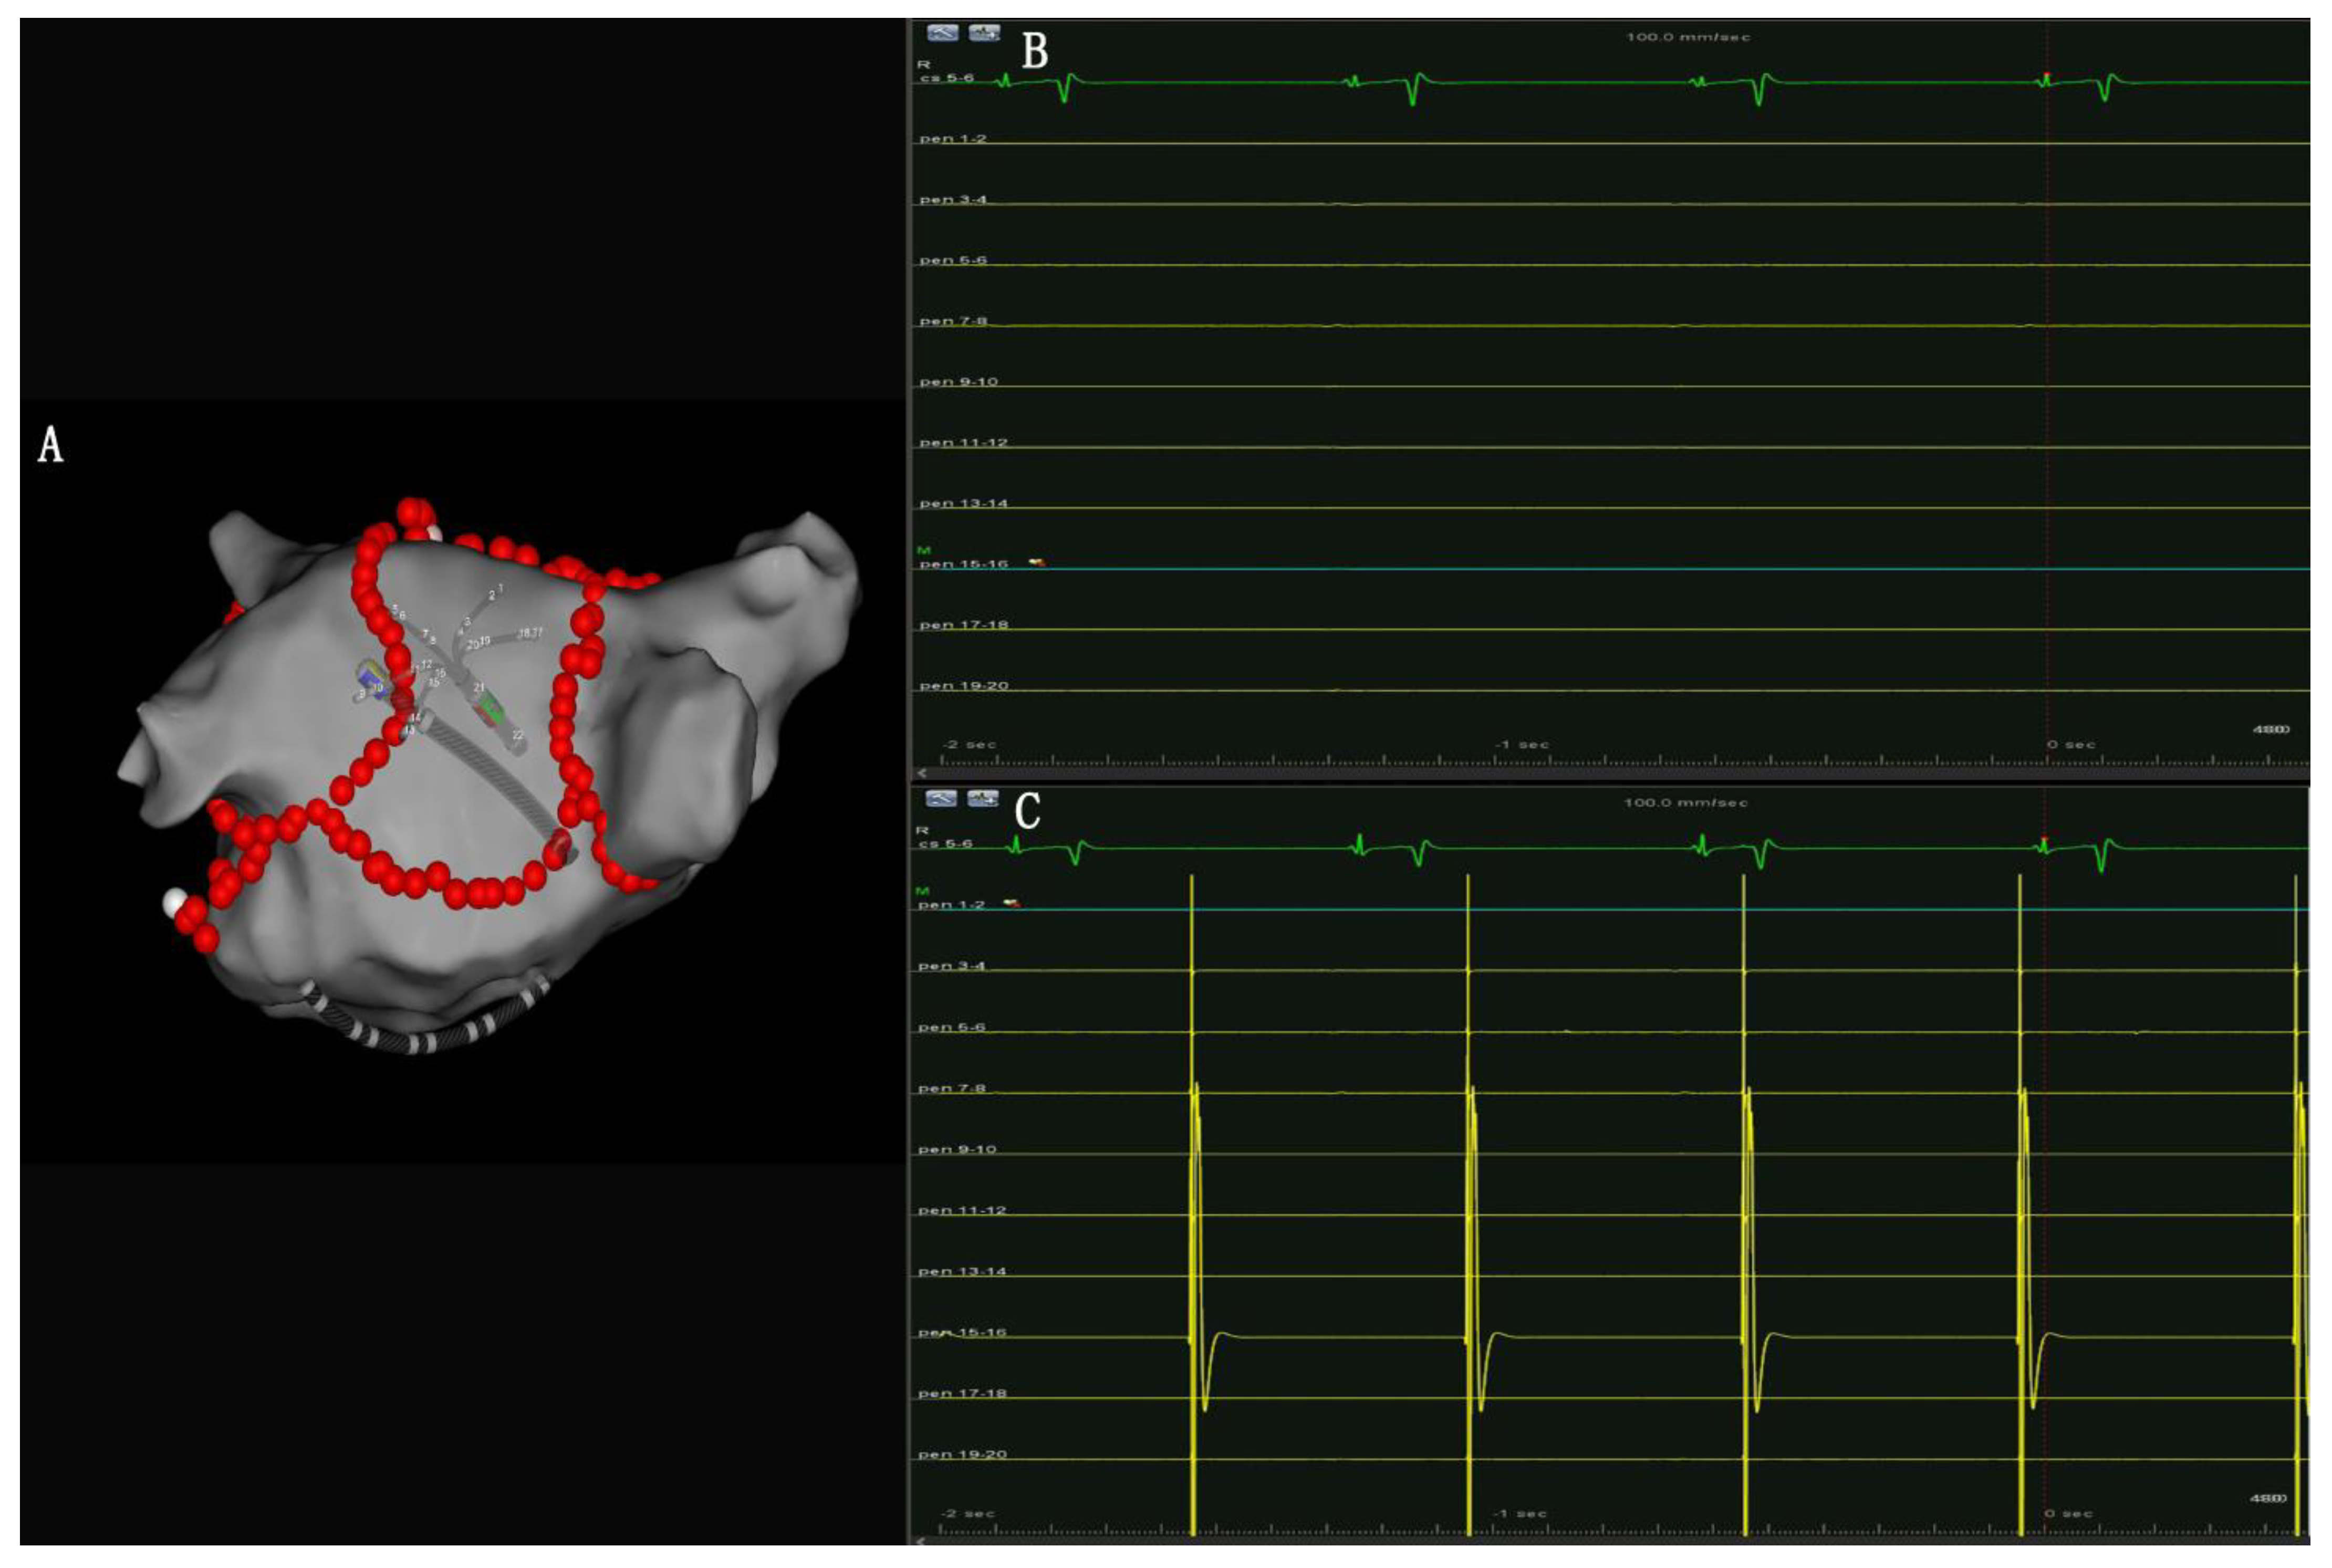

- PW conduction block: After the roof and posterior inferior ablation lines had been completed, the PWI was confirmed with either the electrical silence of the LA posterior wall (Figure 3B), or a conduction block when pacing the LA post wall. (Figure 3C). If the LA posterior wall was not isolated, additional ablations were performed until PWI was achieved.